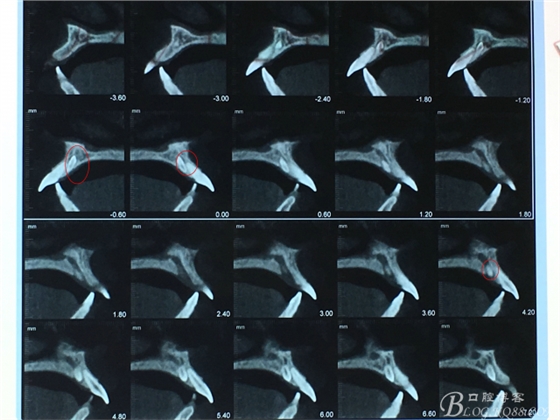

圖4.CBCT檢查:21根尖區(qū)的多生牙位于鼻腭管內(nèi)